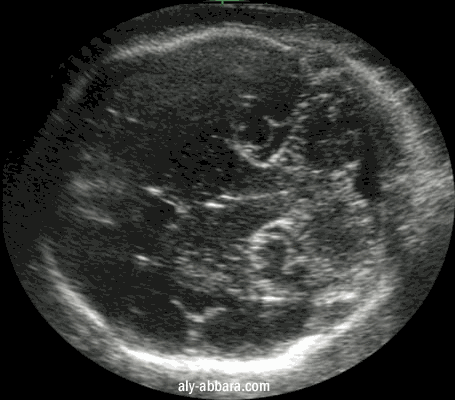

Coupe coronale au niveau du crâne fœtal à 31 SA mettant en évidence le cervelet

et la technique de mesure du diamètre transversal et antéro-postérieur du cervelet